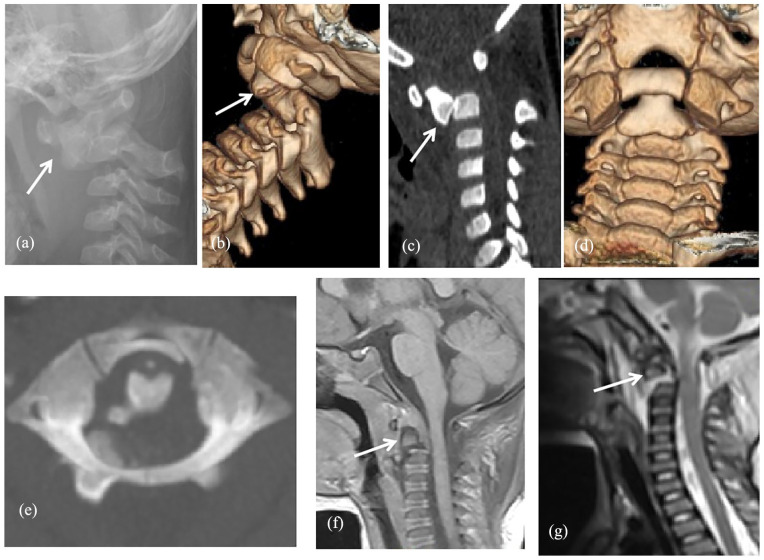

Results: We treated three patients (boy:girl = 0:3, mean age = 2.5 years old) from 2017 to 2020, the diagnoses were all traumatic C1-2 infra-anterior dislocations associated with odontoid fracture (Anderson and D'Alonzo classification type II: three cases, Hosalkar type IB: two case and IC: one case), with or without cervical spinal cord injury. The C1-2 infra-anterior dislocations were all successfully reduced by gentle traction with the halo method (case 1) or occipital-jaw (cases 2 and 3) for a mean of 18.3 days (19, 15, 21 days), after which the Calot plaster vests (head-neck-chest plaster vests) were fitted and maintained for 2 months, without operation. Braces were maintained for 3 months after the Calot plaster vests were removed. All patients achieved fracture healing and recovered from the spinal injury.

Conclusion: In young children, atlantoaxial joint infra-anterior dislocation complicating odontoid fracture usually occurred at the odontoid synchondrosis and belonged to Anderson and D'Alonzo classification type II or Hosalkar type I. Conservative treatment achieved good results (dislocation reduction, bone healing, recovery of neurological symptoms).